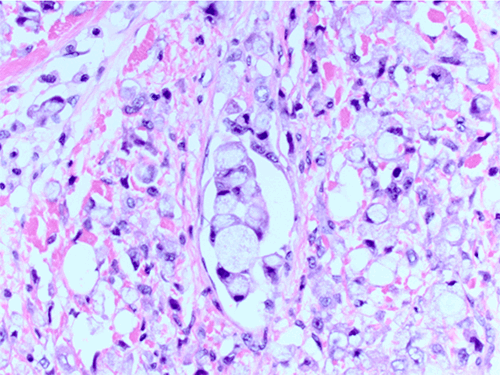

Cell ring

Cell ring 146 фото